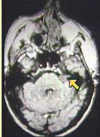

What type of herniation is depicted? Uncal Central (transtentorial) Cingulate (Subfalcine) Transcalvarial Upward cerebellar (transtentorial) Downward cerebellar (Tonsillar)

What type of herniation is depicted? **Uncal** Central (transtentorial) Cingulate (Subfalcine) Transcalvarial Upward cerebellar (transtentorial) Downward cerebellar (Tonsillar) Uncal herniation. Arrows point to the medial temporal lobe that has herniated through the tentorial incisura to compress the midbrain